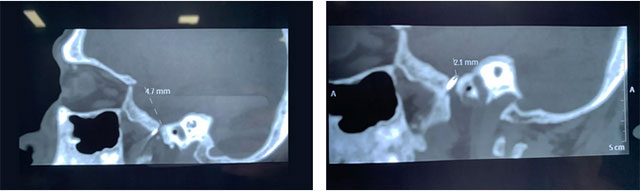

在明确告知手术风险并由患者家属签字确认后,杜立功医生在刘伟钦主任的协助下,为程老伯开展了微创治疗。患者局部麻醉状态下,杜立功在CT引导下将射频针穿刺进靶点,并一点点调整方向,穿刺进入患者左侧半月节。通过一系列专业的电生理测试,选择合适的点位进行多点治疗。历时半小时的治疗后,患者的疼痛得到明显缓解。术后一周,经检查程老伯身体状况良好,三叉神经痛未再发作。